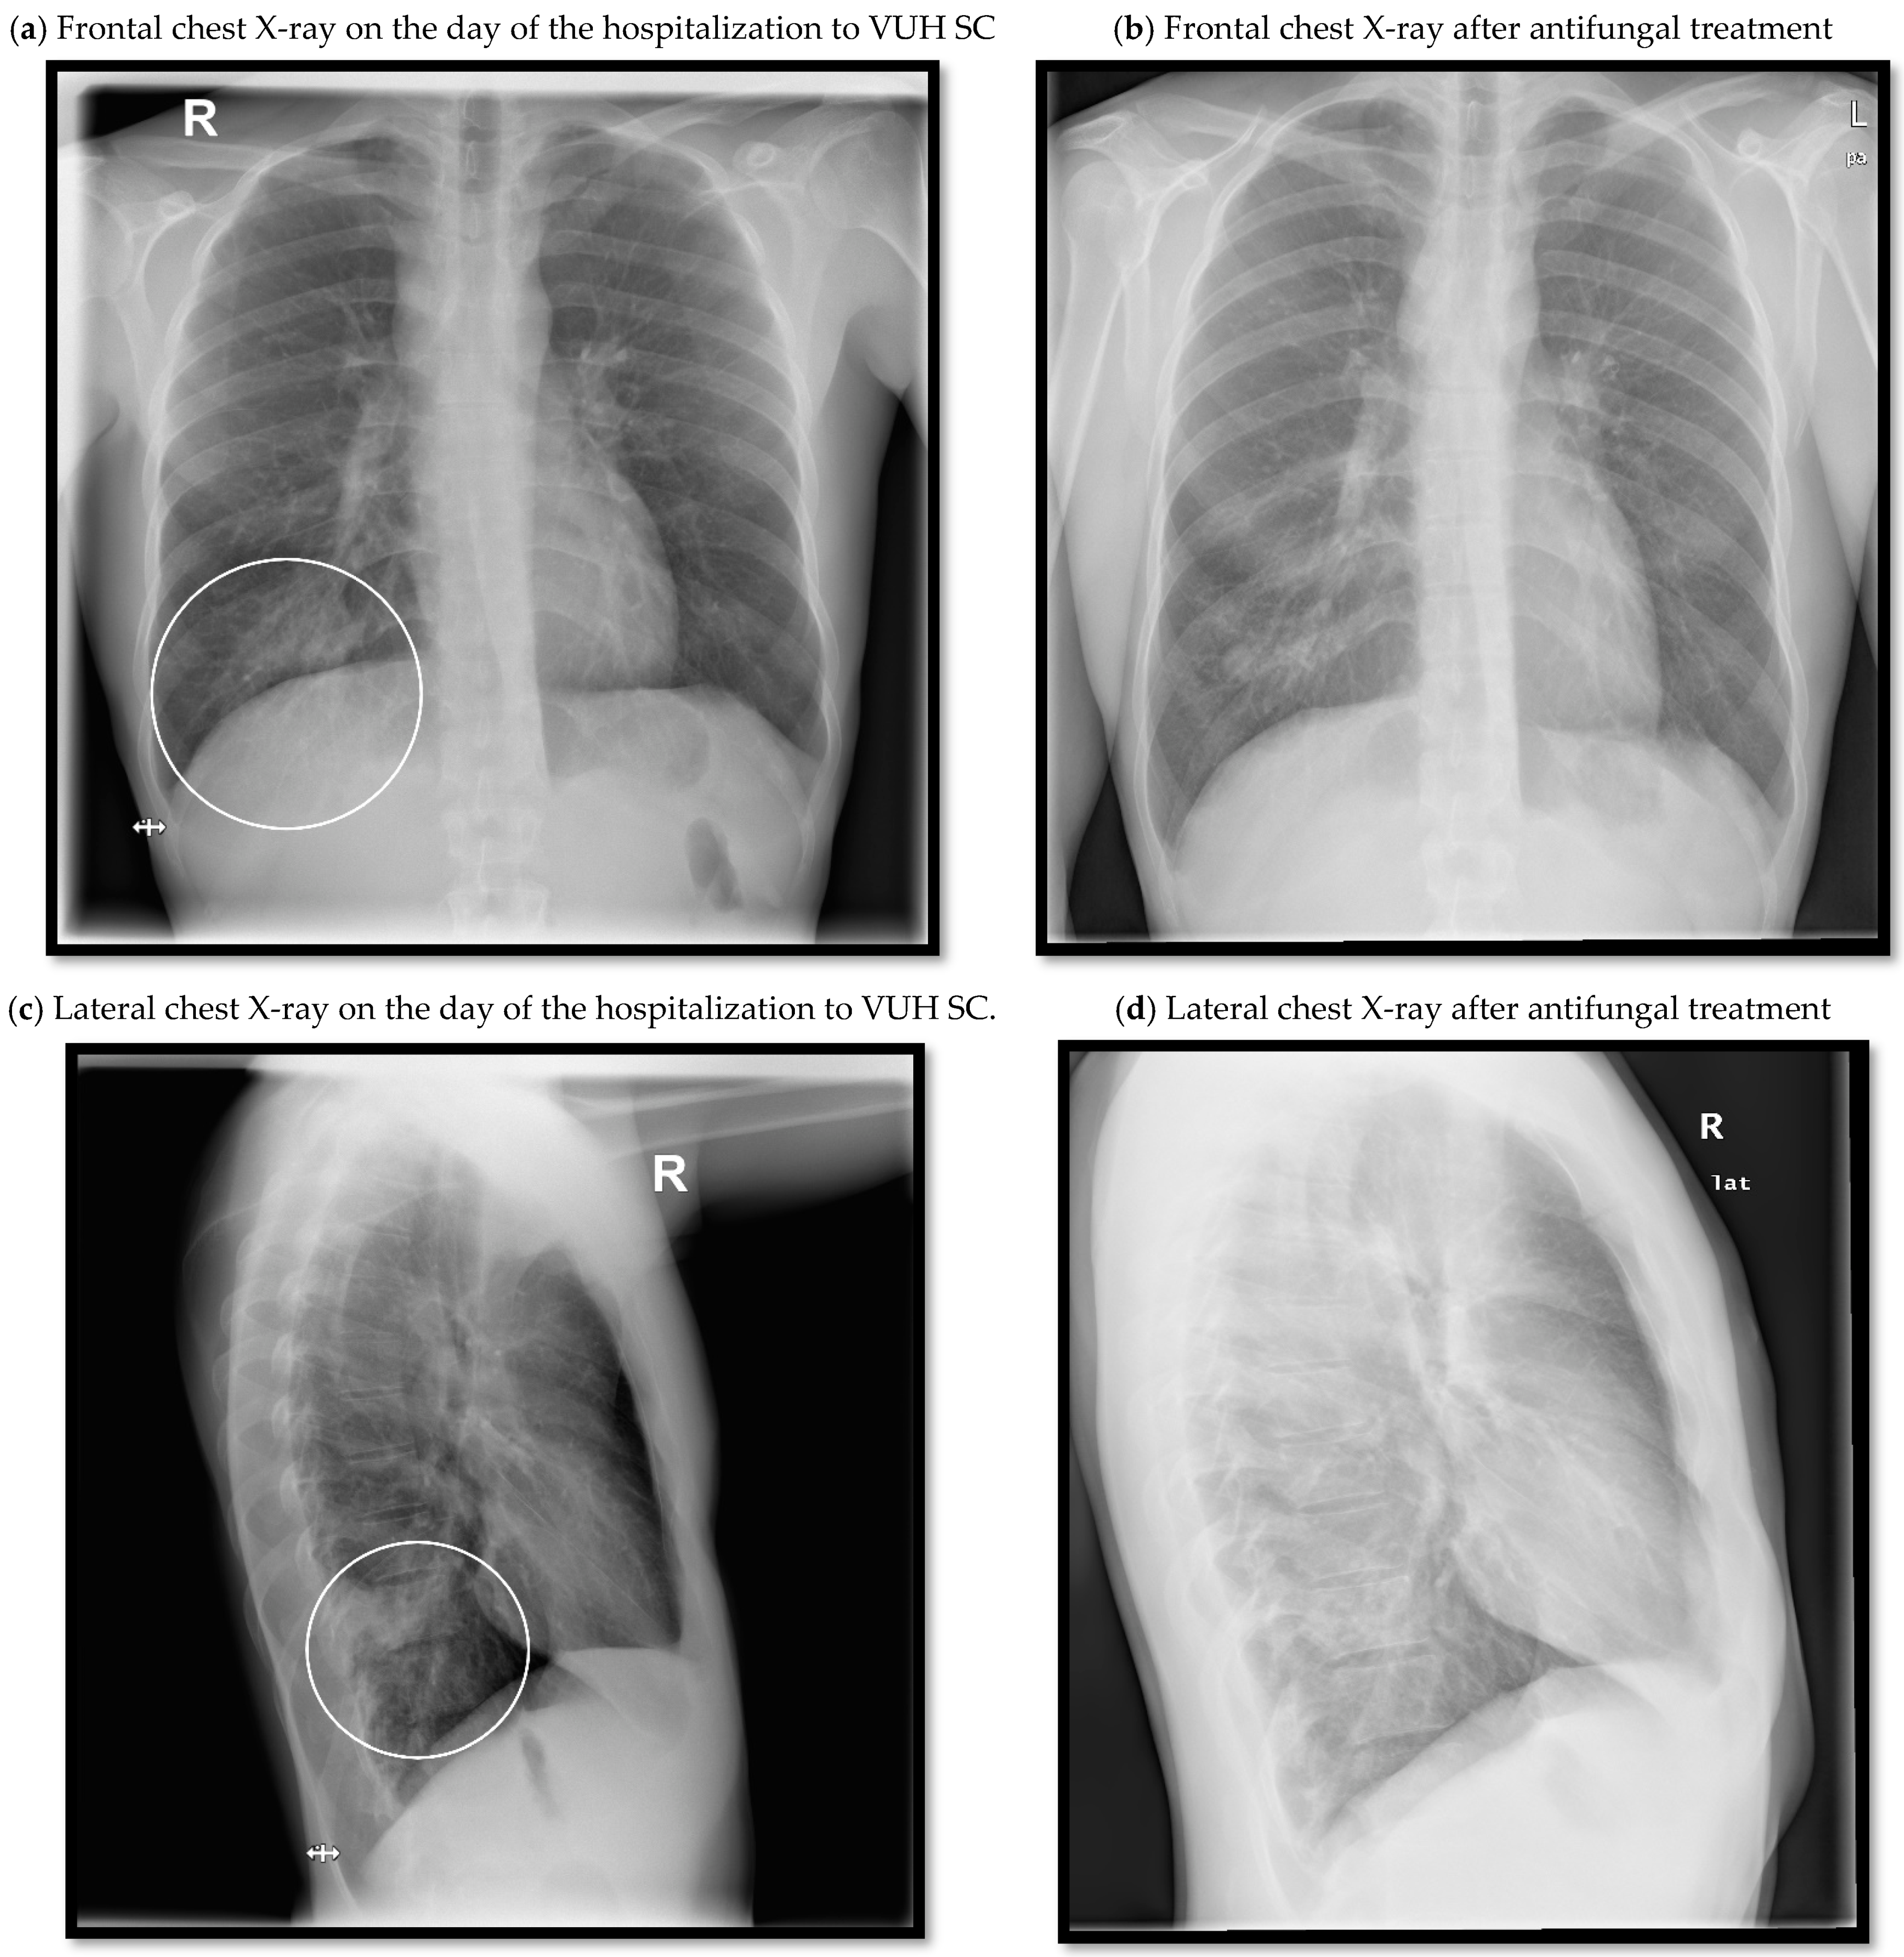

2. Case Report